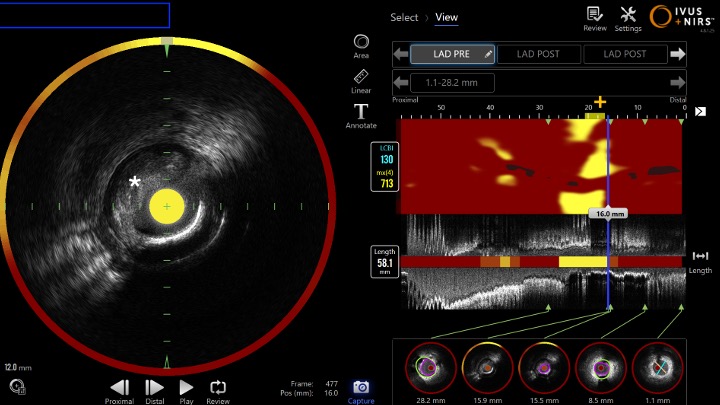

Invasive coronary angiography demonstrated a 95% stenosis in the proximal left anterior descending artery. Combined Near Infrared Spectroscopy (NIRS) and Intravascular Ultrasound (IVUS) imaging identified minimal calcification with features consistent with plaque rupture, therefore identifying the culprit lesion as the cause of the cardiac arrest.

After administration of 180 mg ticagrelor and 8000 IU heparin, the lesion was crossed. Pre dilatation was performed using a 3.5 mm non compliant Trek (Abbott, California, USA) balloon. Makoto NIRS-IVUS DualPro (InfraredX - Nipro Corp, Massachusetts, USA) imaging revealed minimal calcification and clear evidence of plaque rupture with a large lipid core burden index (LCBI = 700). An Onyx Frontier drug eluting stent (Medtronic, Ireland) was deployed near to the ostium. Post dilatation was performed with a 3.5 mm and 4.0 mm noncompliant balloon.

- Near Infrared Spectroscopy (NIRS) and IVUS image showing lipidic plaque and rupture

* = site of plaque rupture

+ = site of maximum lipid arc (yellow) --> measured as LCBI (Lipid Core Burden Index)